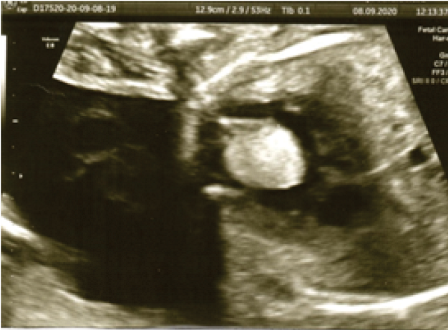

Rhabdomyomas are rare fetal cardiac tumours that may be present in up to 86 % of newborns. They are mostly found in the interventricular septum, atrial or ventricular free wall and infrequently in the atrioventricular valves. It depends on the size of the tumour to have fetal haemodynamic repercussions.

Ultrasound examination shows a hyperechogenic lesion in the interventricular septum with protrusion into the right ventricular cavity, accompanied by mild deviation of the interventricular septum and associated at the time of examination with ventricular arrhythmia.